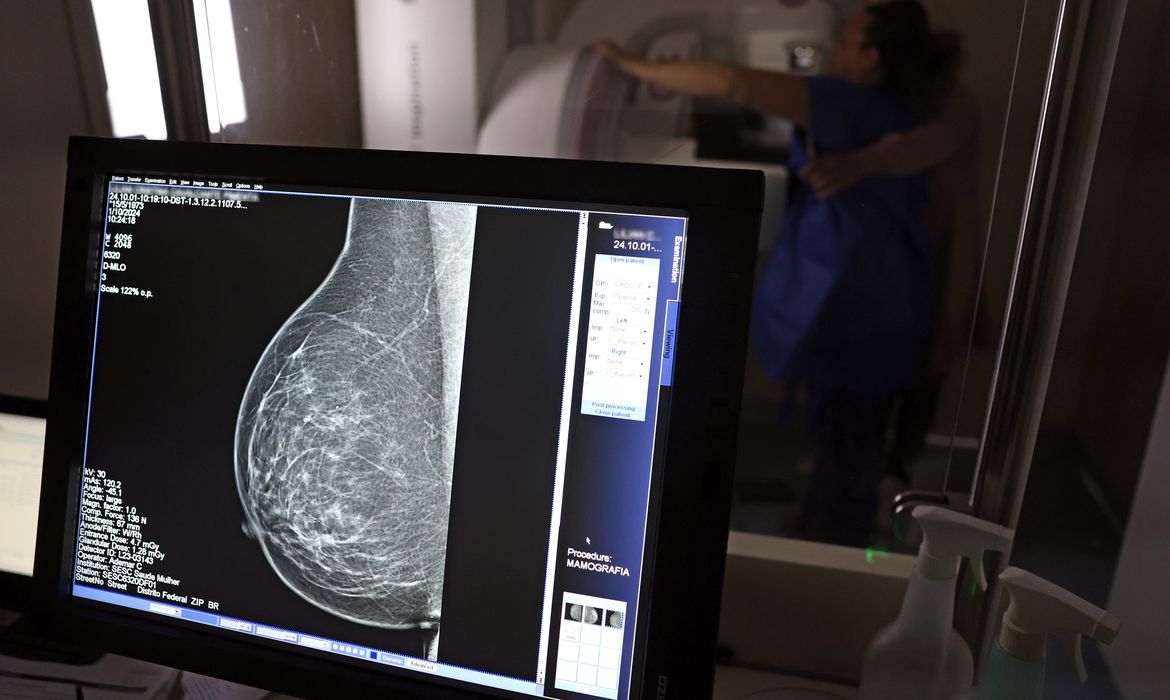

No Outubro Rosa, o Instituto Nacional de Câncer (Inca) estimou 73.610 novos casos este ano no país. É o câncer que mais mata mulheres no Brasil. As mulheres em tratamento pela doença têm o direito de receber o auxílio-doença ou o benefício de prestação continuada. A vice-presidente da Comissão de Previdência Social Pública da Ordem dos Advogados do Brasil do Rio de Janeiro (OAB-RJ), Danielle Guimarães, destaca que o câncer de mama é uma das doenças que mais afetam mulheres no Brasil, impactando não apenas a saúde física e emocional, mas também a capacidade de trabalho e a segurança financeira das pacientes. “Nesse contexto, conhecer os direitos previdenciários é essencial para garantir proteção social, dignidade e amparo durante o tratamento. A legislação brasileira oferece mecanismos específicos de amparo às mulheres acometidas pelo câncer de mama, entre eles o benefício por incapacidade temporária, aposentadoria por incapacidade permanente e o benefício de prestação continuada (BPC/LOAS)”, diz a advogada. Auxílio-doença A lei prevê que o auxílio-doença será devido ao segurado que ficar incapacitado para o seu trabalho por mais de 15 dias consecutivos Segundo Danielle, o auxílio por incapacidade temporária, conhecido como auxílio-doença, destina-se a seguradas que ficam temporariamente incapacitadas para exercer suas atividades profissionais devido ao câncer de mama ou aos efeitos do tratamento (cirurgias, quimioterapia, radioterapia e seus efeitos físicos e emocionais). Ela explica, que, nos casos de câncer, não há exigência de carência, conforme previsto no artigo 26, inciso II, combinado com o artigo 151 da Lei nº 8.213/91, que elenca as doenças graves. Basta que a segurada mantenha a qualidade de segurada (empregada, contribuinte individual, doméstica, facultativa ou segurada especial); Comprove a incapacidade para o trabalho, mediante laudos, atestados e relatórios médicos detalhados. Aposentadoria por incapacidade permanente Quando o câncer de mama é maligno e causa incapacidade total e definitiva para o trabalho, a segurada pode requerer a aposentadoria por incapacidade permanente (antiga aposentadoria por invalidez), prevista no artigo 42 da Lei nº 8.213/91. Também neste caso, não há carência mínima, bastando comprovar a incapacidade total e a qualidade de segurada. A concessão depende de perícia médica do INSS, que avaliará se a segurada está incapaz de exercer qualquer atividade profissional de forma definitiva. “Estes benefícios garantem dignidade humana e segurança financeira às mulheres que estejam em tratamento enquanto durar a incapacidade ou não podem mais retornar ao mercado de trabalho devido à gravidade da doença”, afirma a advogada previdenciária.  Benefício De acordo com Danielle, quem não contribui para o INSS e tem câncer de mama pode ter direito ao Benefício de Prestação continuada (BPC/LOAS), previsto na Lei 8.742/93.  Para ter acesso, é preciso comprovar a vulnerabilidade social e a deficiência causada pela doença.  Requisitos para o BPC/LOAS Impedimento de longo prazo: a doença deve causar tratamento temporário de longo prazo (com duração mínima de 2 anos) ou diagnóstico de doença grave ou deficiência definitiva. Hipossuficiência econômica: a renda familiar per capita deve ser igual ou inferior a um quarto do salário-mínimo. Esse valor pode ser flexibilizado, levando em conta os gastos com a doença, como medicamentos e consultas. Não ter outros benefícios previdenciários: Não é possível receber outro benefício previdenciário ao mesmo tempo.  Como requerer os benefícios O requerimento deve ser feito exclusivamente pelos canais oficiais do INSS: Site ou aplicativo Meu INSS Telefone do INSS 135 A segurada deve reunir os seguintes documentos: Identidade e CPF; Comprovante de vínculo previdenciário (CTPS, carnês de contribuição, CNIS); Laudos, exames e relatórios médicos que comprovem a doença e a incapacidade; Relatório médico indicando o tempo estimado de afastamento (no caso do auxílio-doença). No caso de negativa do INSS, a segurada pode interpor recursos pelas vias administrativa ou judicial. “Os benefícios de incapacidade temporária e incapacidade permanente representam mais do que uma compensação financeira. São instrumentos de proteção social, dignidade e cuidado com a saúde, permitindo que a mulher se dedique ao tratamento sem preocupações econômicas”, completa a advogada previdenciária. A presidente da Comissão de Direito Médico da OAB-RJ, Carolina Mynssen, lembra que o paciente de câncer tem direito ao tratamento em até 60 dias. “Se ela tem o diagnóstico, ela em até 60 dias tem o direito de iniciar o tratamento. Se isso não acontecer, tem que entrar com ação judicial. A pessoa também tem o direito de fazer o tratamento fora do seu município, caso não tenha especialista na sua cidade. O paciente com doença grave tem também tem o direito de acesso a medicamentos”, disse a advogada. O portador de doença grave como tuberculose ativa, hanseníase, alienação mental, esclerose múltipla, hepatopatia grave, neoplasia maligna (câncer), cegueira, paralisia irreversível e incapacitante, cardiopatia grave, doença de Parkinson, espondiloartrose anquilosante, nefropatia grave, estado avançado da doença de Paget (osteíte deformante), síndrome da deficiência imunológica adquirida (aids) ou contaminação por radiação tem o direito de sacar o Fundo do Garantia do Tempo de Serviço (FGTS).  A advogada da área médica também destaca que os portadores de doenças graves têm direito à isenção do imposto de renda no salário ou na aposentadoria. “São muitos meses ou anos de tratamento, a pessoa, muitas vezes, não consegue retornar à atividade laboral. Assim, com a isenção do imposto de renda, ela passa a ter menos cortes no rendimento que obviamente vai ser impactado pela necessidade do tratamento”, disse Carolina. Relacionadas Falta de acesso a mamógrafos limita prevenção do câncer de mama Brasil recebe lote de medicamento para tratar câncer de mama no SUS Vacina contra HPV reduz em 58% casos de câncer de colo de útero